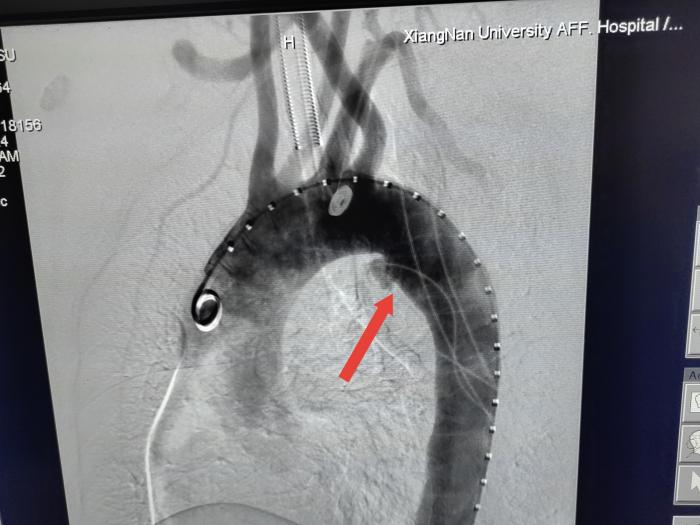

依据术前CTA测量动脉长度、直径、角度、距离及开口位置,术中造影再次确认,治疗团队根据所测数据先对支架进行“双开窗”改装,在支架上裁剪出与对应的左、右锁骨下动脉出口等圆的两个小洞。开弓没有回头箭,支架上的“窗户口子”一旦打开就无法复原。最终,医务人员凭借精确测量和娴熟手法攻克了这个难关,成功完成体外“双开窗”手术。最后在主动脉造影下精准定位血管位置,成功释放支架,顺利实现了病变区完全隔绝,所有分支完整保留。